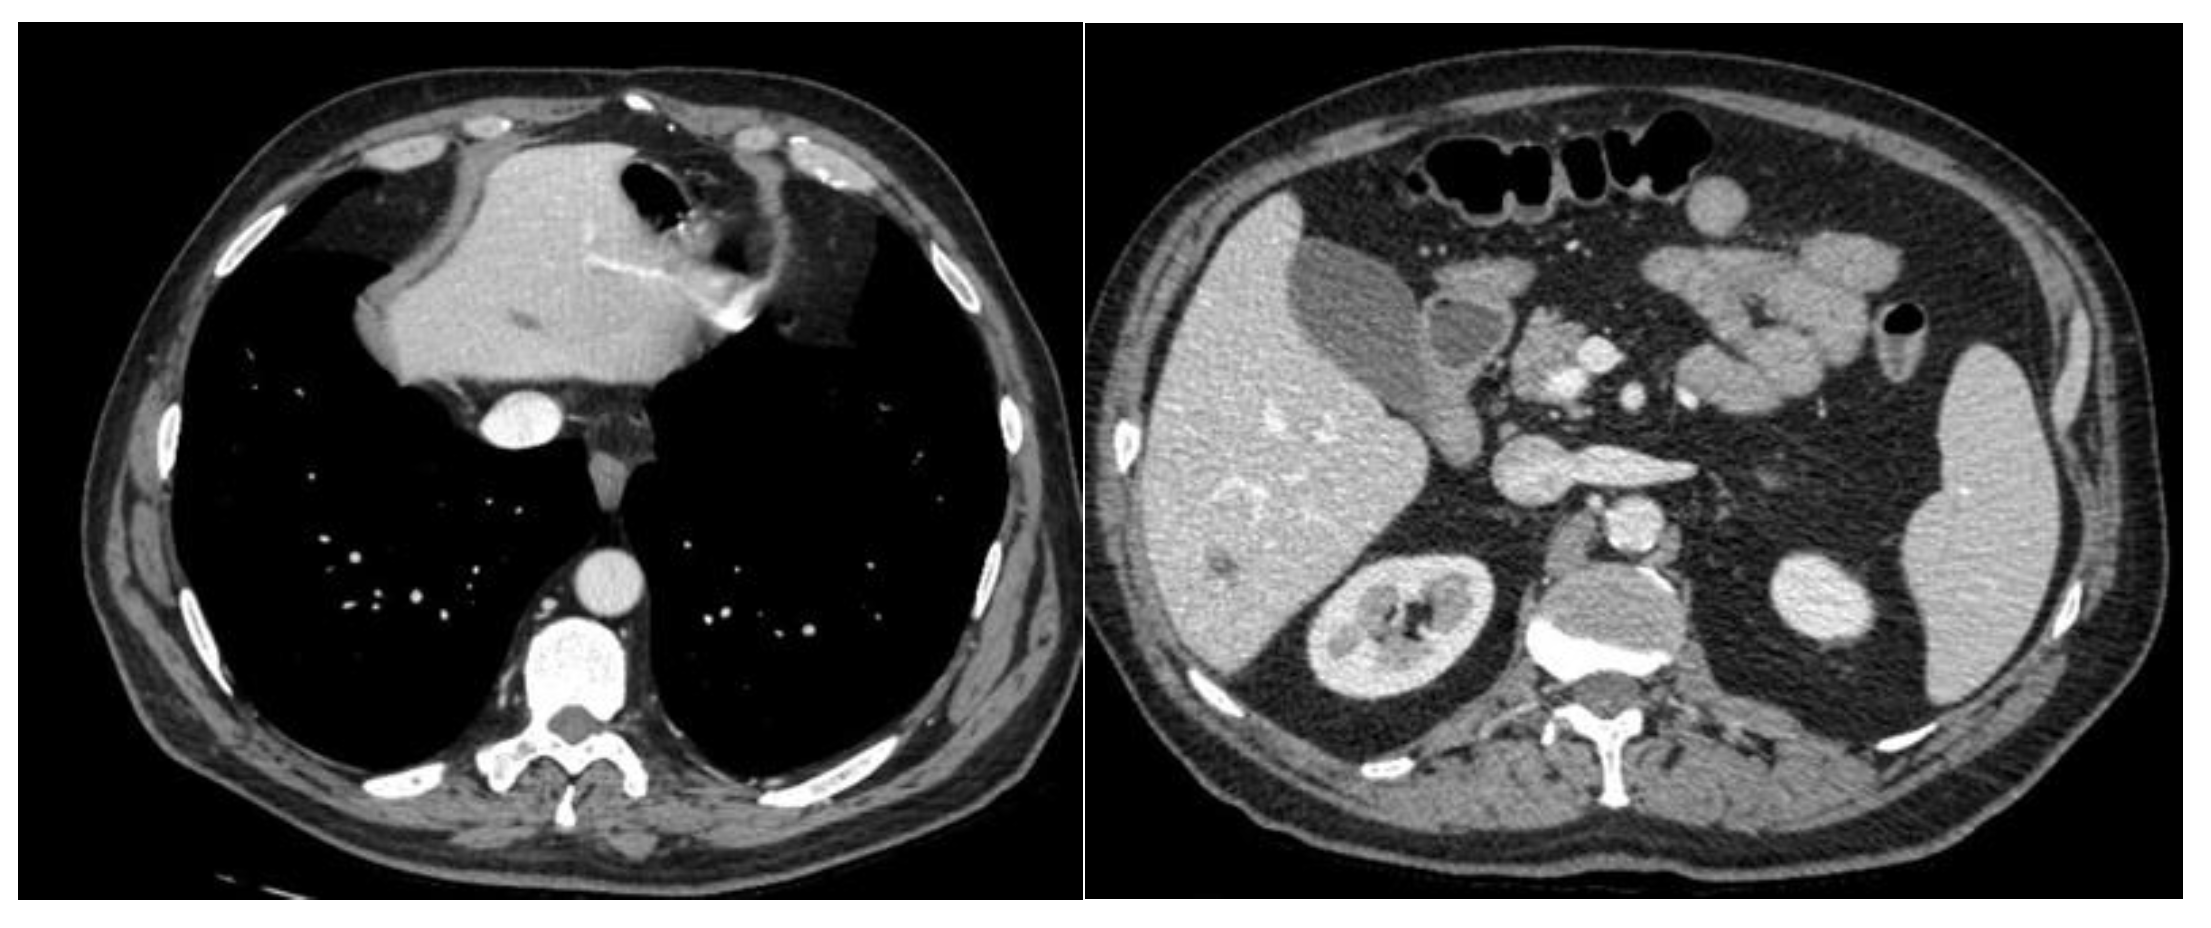

A CT scan was performed with evidence of Multiple hepatic and bilateral nodal metastases [Figure 1].

Figure 1. Basaline CT.